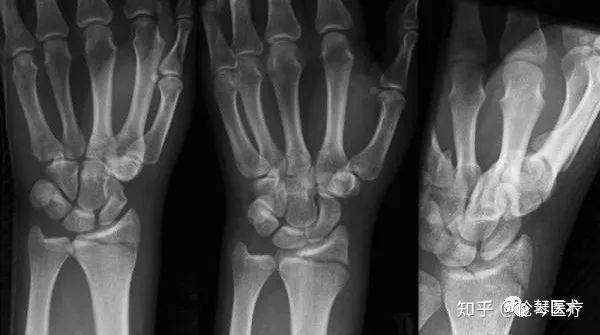

fracture▼拳击手骨折boxers fracture▼舟骨骨折▼正常腕关节▼

指骨骨折▼bennett fracture▼拳击手骨折boxers fracture▼舟骨骨折

发于第4,5掌骨,因为拳击手比赛时,容易发生此类损伤,故称为拳击手骨折

boxers knuckl拳击手指节拳击手骨折是发生于掌骨的骨折,最常见的是